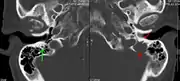

The diagnostic examination of a person with suspected multiple myeloma typically includes a skeletal survey. This is a series of X-rays of the skull, axial skeleton, and proximal long bones. Myeloma activity sometimes appears as "lytic lesions" (with local disappearance of normal bone due to resorption) or as "punched-out lesions" on the skull X-ray ("raindrop skull"). Lesions may also be sclerotic, which is seen as radiodense.[70] Overall, the radiodensity of myeloma is between −30 and 120 Hounsfield units (HU).[71] Magnetic resonance imaging is more sensitive than simple X-rays in the detection of lytic lesions, and may supersede a skeletal survey, especially when vertebral disease is suspected. Occasionally, a CT scan is performed to measure the size of soft-tissue plasmacytomas. Nuclear Medicine Bone scans are typically not of any additional value in the workup of people with myeloma (no new bone formation; lytic lesions not well visualized on nuclear bone scan).

A CT of the brain revealed a lytic lesion in the left temporal bone (right side of image), and petrous temporal bones involving the mastoid segment of the facial nerve canal. Red arrows: lesion; green arrow: normal contralateral facial nerve canal. The lesions are consistent with a myeloma deposit.